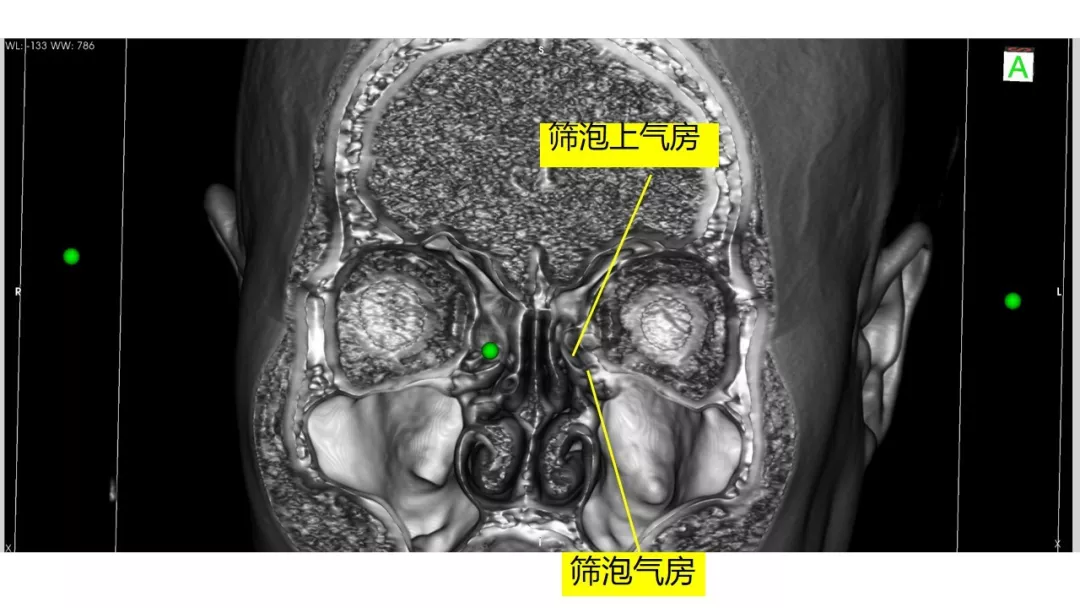

Osirix冠矢轴